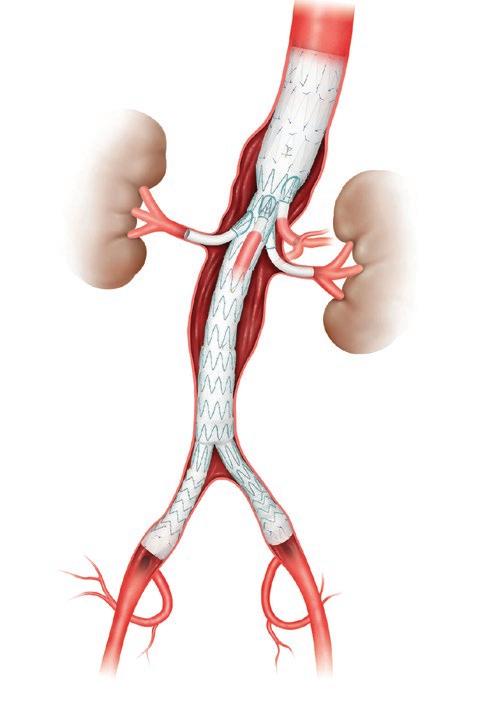

Minimally invasive endovascular repair makes for safer and more effective repair of complex aortic aneurysms, especially those that include the arteries branching to the brain, arms, intestines and kidneys.

Surgeons at UMass Memorial Health’s Center for Complex Aortic Disease are advancing both fenestrated and branched forms of endovascular aortic repair (EVAR) techniques. These involve only two groin needle punctures, rather than open surgical repair, making the procedures safer and recovery faster for patients.

During a complex fenestrated or branched endovascular aortic aneurysm repair, the surgeon delivers a custom-made, expandable stent graft (above) to the area of the aneurysm. Small holes in the endograft are configured at the exact location of the branch arteries to accommodate the addition of smaller stent grafts to those arteries.

The minimally invasive FEVAR technique makes for safer and more effective repair of complex aortic aneurysms that include the arteries branching to the kidneys and intestines. The stent graft is designed to accommodate more complex aortic anatomy. Small holes in the endograft

are configured at the exact location of the branch arteries to accommodate the addition of smaller stent grafts to those arteries. The fenestrated endograft must align with the patient’s particular anatomy.